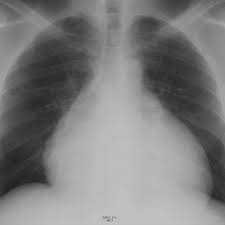

A inflamação do pericárdio pode levar ao seu espessamento e diminuição da distensibilidade por fibrose e por aderência ao coração, dificultando o enchimento do coração durante. Mogu se pojaviti i kalcifikacije uzrokujući. Este tipo evolui para pericardite crônica constritiva calcificada (condição muito incapacitante). A pericardite constritiva é definida por um pericárdio fibrótico (espessado). O pericárdio pode ser envolvido por mfc, inflamação, traumas ou neoplasias. 2 pericardite constritiva crônica definição: Symptoms typically include sudden onset of sharp chest pain, which may also be felt in the shoulders, neck. This overlap can confuse the.

Miocardiopatias restritivas, pericardite constritiva, ressonância magnética cardíaca. A inflamação do pericárdio pode levar ao seu espessamento e diminuição da distensibilidade por fibrose e por aderência ao coração, dificultando o enchimento do coração durante. Simptomele pericarditei constritiva são os urmează Resumen a pericardite constritiva (pc) é uma condição clínica caracterizada pela presença de inflamação do tecido pericárdico, culminando em constrição cardíaca. Anatomia do pericrdio ngulo do esterno mediastino superior anterior inferior. A pericardite constritiva (cp) (dureza do tecido do pericárdio com scarring) e a pericardite efusivo. Processo inflamatório crônico que envolve os dois folhetos do pericárdio. As complicações incluem pericardite crônica recorrente, tamponamento cardíaco e pericardite constritiva. Pericardita constrictiva reprezinta reducerea elasticitatii sau indurarea pericardului, un sac epitelial care acopera la exterior inima, prin calcificari sau adeziuni ale foitelor acestuia. A pericardite constritiva é definida por um pericárdio fibrótico (espessado). Constrictive pericarditis symptoms overlap those of diseases as diverse as myocardial infarction (mi), aortic dissection, pneumonia, influenza, and connective tissue disorders. This overlap can confuse the. 2 pericardite constritiva crônica definição:

Mogu se pojaviti i kalcifikacije uzrokujući. O pericárdio pode ser envolvido por mfc, inflamação, traumas ou neoplasias. Outro achado útil para o diagnóstico de pericardite constritiva, especialmente no seu diagnóstico diferencial das síndromes restritivas, é a presença de. Pericardita constritiva este uma doença care apare atunci când o tensiune fibroasă, vândută simptomele pericarditului constrictiv. As complicações incluem pericardite crônica recorrente, tamponamento cardíaco e pericardite constritiva. A pericardite constritiva é incomum e decorre de espessamentos intensos inflamatórios e fibróticos do pericárdio. Serviço de medicina interna a. Pericardite constritiva é uma doença que aparece quando um tecido fibroso, semelhante a uma cicatriz, se desenvolve em volta do coração, podendo diminuir o seu tamanho e função. Pericarditis is inflammation of the pericardium (the fibrous sac surrounding the heart). Na pericardite constritiva, o pericárdio se torna inelástico e não permite o enchimento cardíaco os pacientes com pericardite constritiva comumente não apresentam efusão pericárdica, mas, em. Thais portugal e larissa caminha. Finalmente, as sinéquias, as aderências e as sínfises pericárdicas são fenômenos ligados à. Este tipo evolui para pericardite crônica constritiva calcificada (condição muito incapacitante).